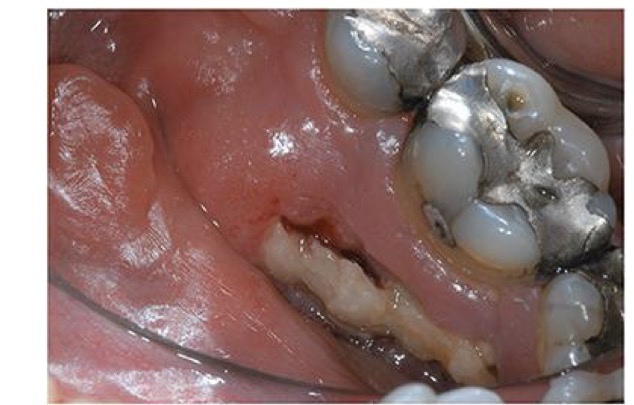

CHẨN ĐOÁN?

HOẠI TỬ XƯƠNG HÀM SAU XẠ TRỊ